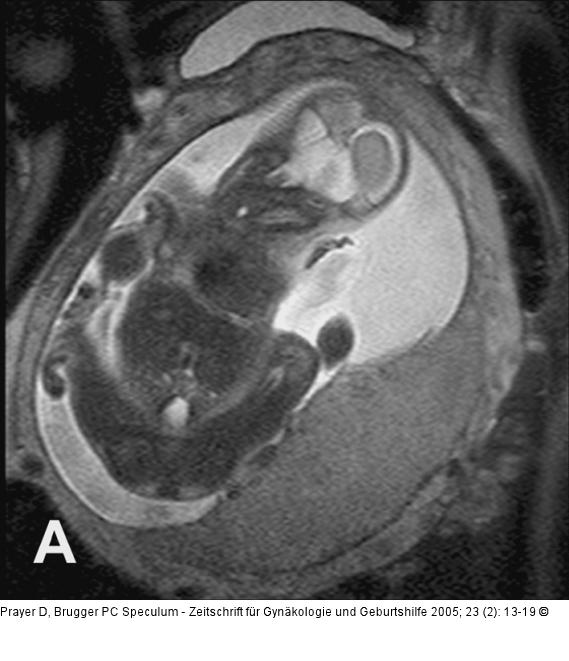

Abbildung 6a-b: Pränatale Magnetresonanztomographie Normale, homogene und glatt begrenzte Plazenta in der 26. SSW. B. gleiche SSW, die Plazenta hat jedoch eine pathologisch unruhige Binnenstruktur und eine unregelmäßige Oberfläche. Der Fetus weist eine Wachstumsrestriktion auf. |

Normale, homogene und glatt begrenzte Plazenta in der 26. SSW. B. gleiche SSW, die Plazenta hat jedoch eine pathologisch unruhige Binnenstruktur und eine unregelmäßige Oberfläche. Der Fetus weist eine Wachstumsrestriktion auf. |